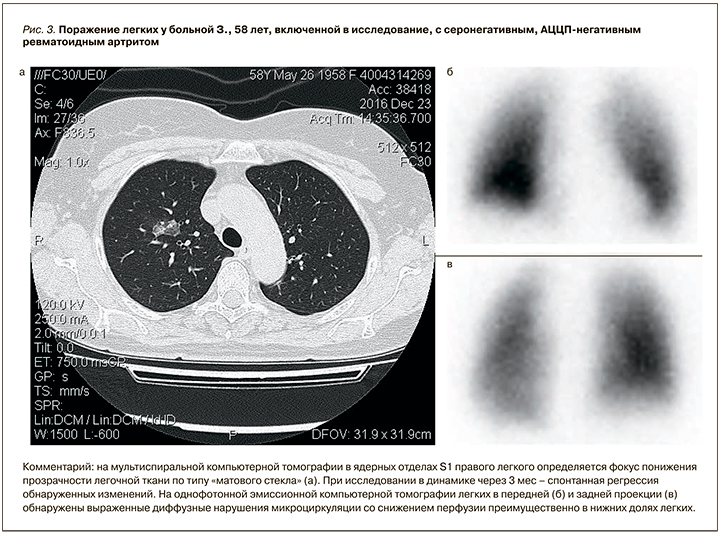

Обнаруженные у пациентов с РА перфузионные нарушения в легких по результатам ОФЭКТ оказались достоверно более выраженными у АЦЦП-негативных пациентов (рис. 3). Как было установлено нами ранее [17], сосудистые нарушения в легких у больных РА могут быть связаны не только с интерстициальным процессом, но и вовлечением бронхиального дерева: когда регионарный кровоток снижается в невентилируемых зонах легких, происходит шунтирование кровотока. Таким образом, более выраженное снижение легочной перфузии у серонегативных больных, очевидно, обусловлено более частым поражением у них бронхиального аппарата. Вероятно, что и легочная гипертензия, обнаруживавшаяся преимущественно у АЦЦП-негативных больных РА, связана в большей степени с перестройкой сосудистого русла легких как осложнением бронхообструктивного процесса.